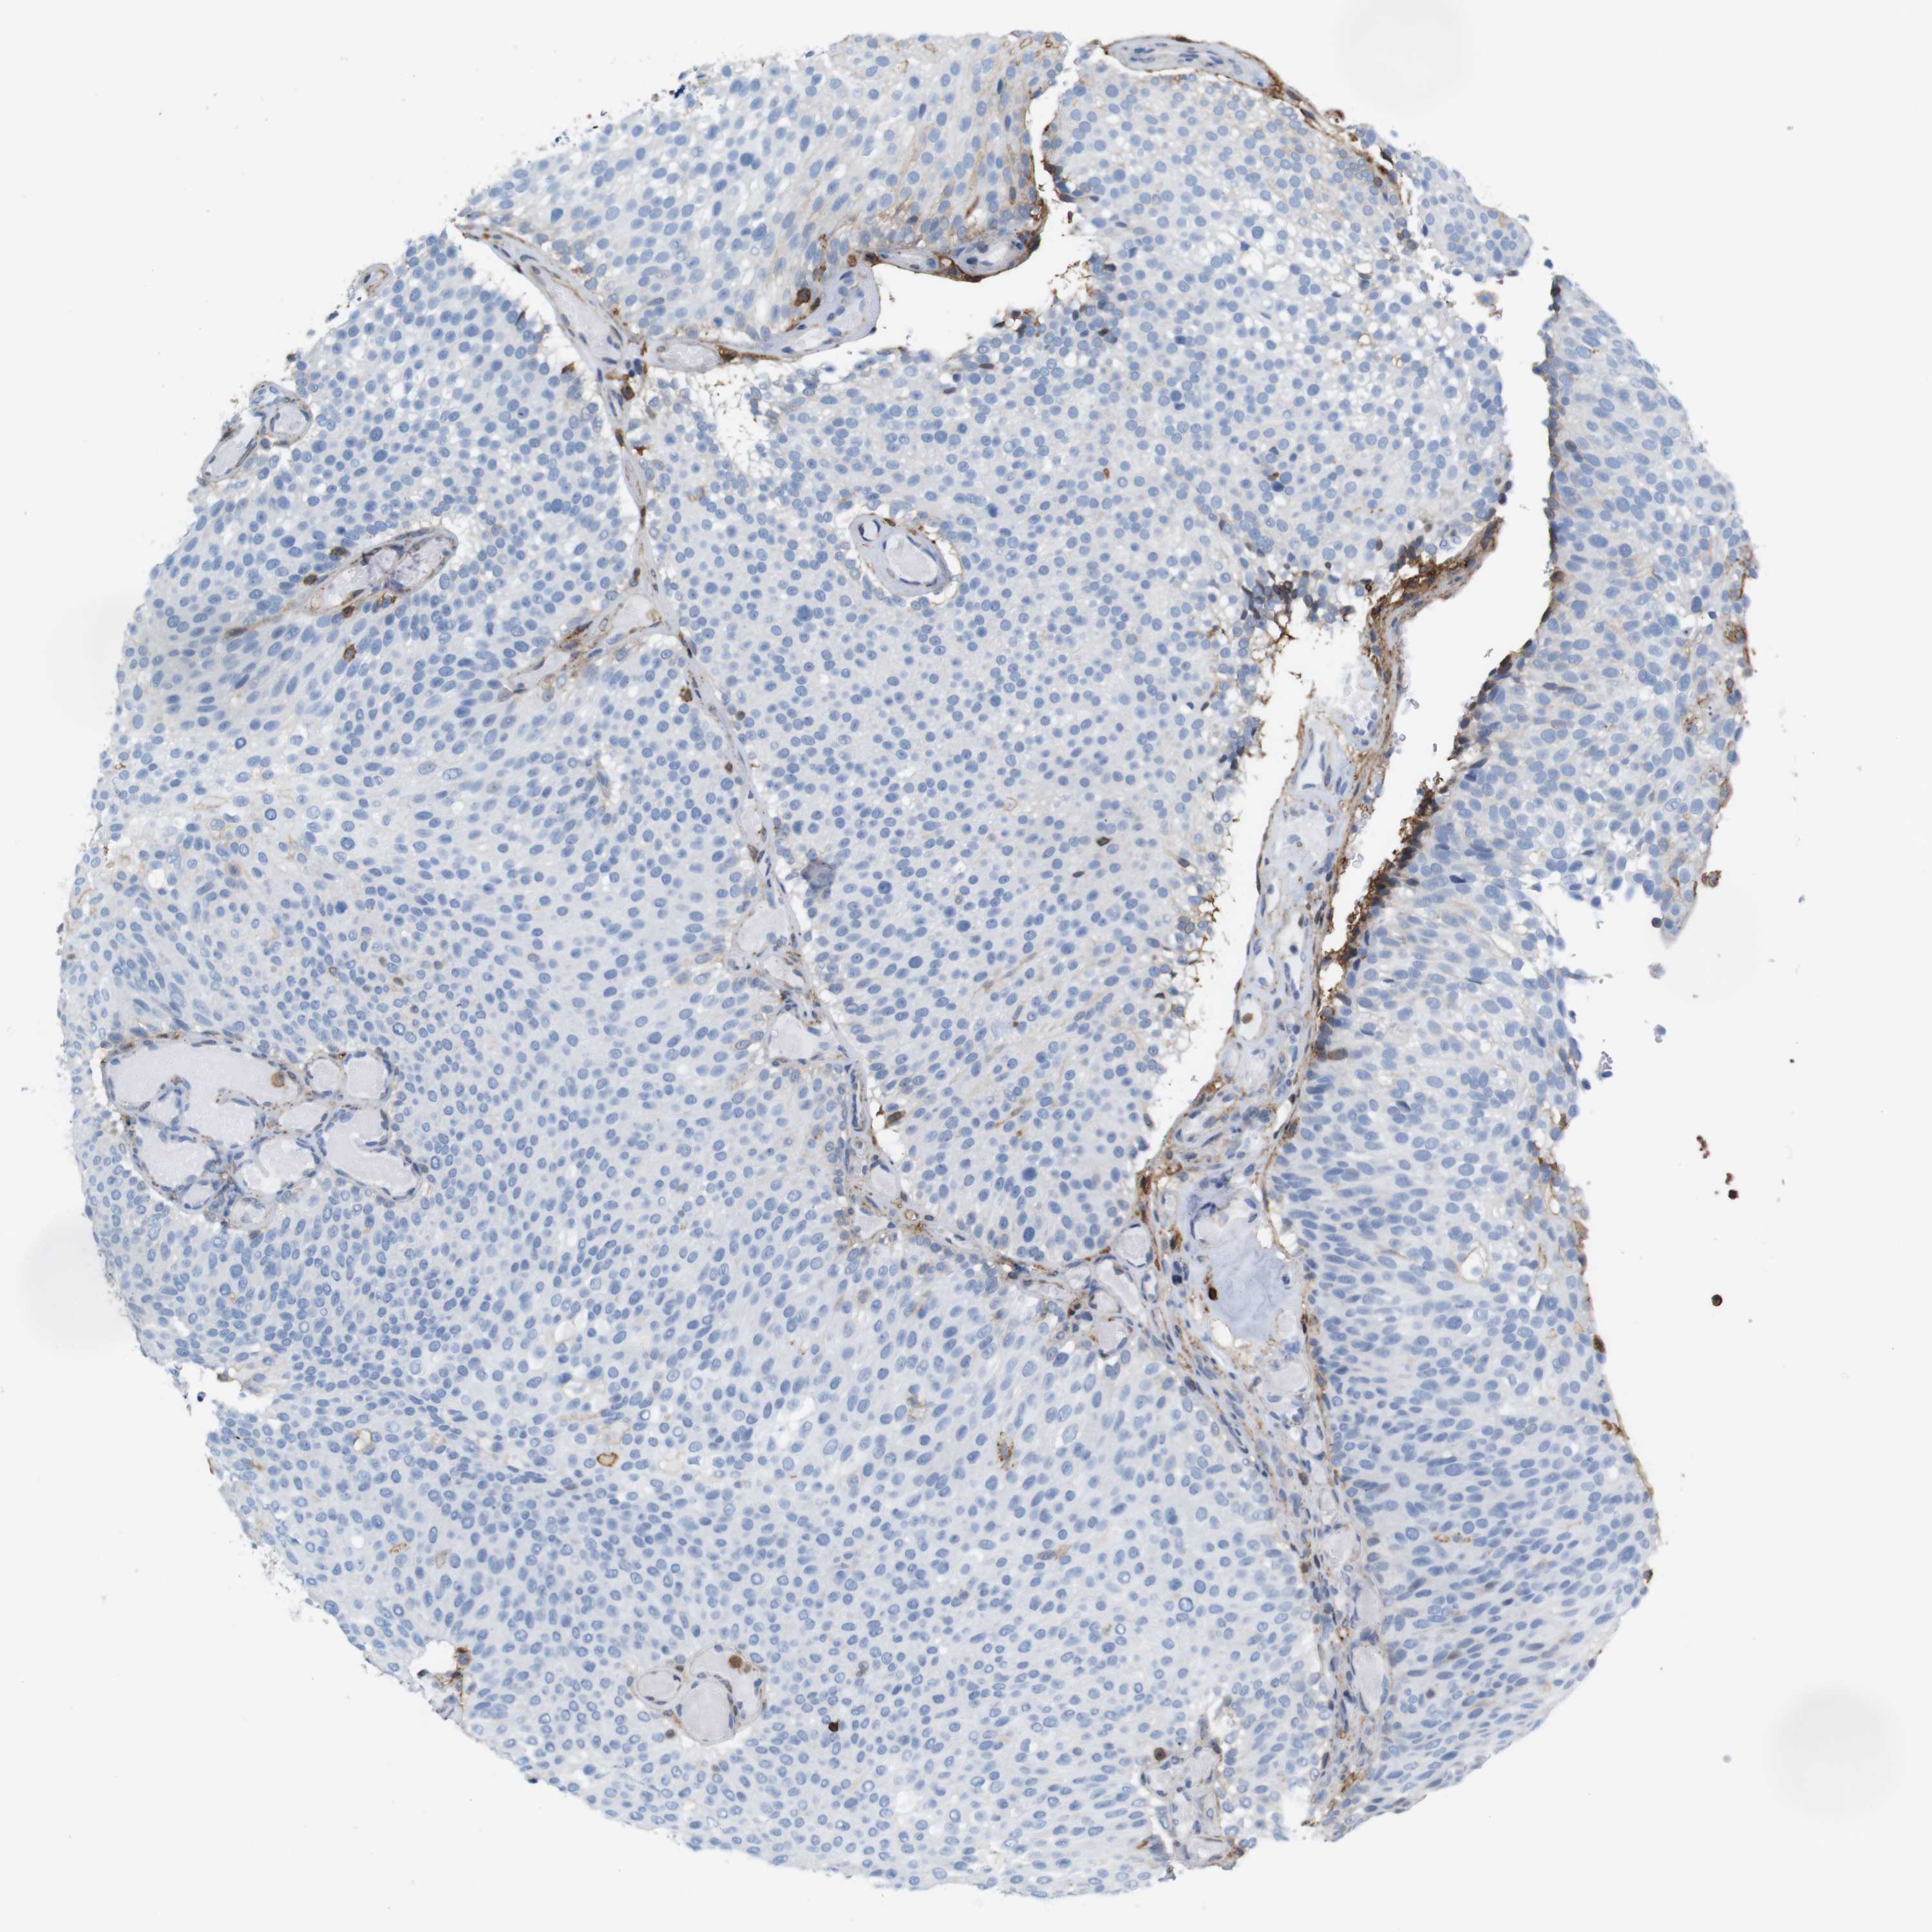

UROTHELIAL CANCER - Protein expressioni

A mouse-over function shows sample information and annotation data. Click on an image to view it in a full screen mode. Samples can be filtered based on level of antibody staining by selecting one or several of the following categories: high, medium, low and not detected. The assay and annotation is described here.

Note that samples used for immunohistochemistry by the Human Protein Atlas do not correspond to samples in the TCGA dataset.

Antibody stainingi

Antibody staining in the annotated cell types in the current human tissue is reported as not detected, low, medium, or high, based on conventional immunohistochemistry profiling in selected tissues. This score is based on the combination of the staining intensity and fraction of stained cells.

Each image is clickable and will lead to virtual microscopy that enables deeper exploration of all samples and also displays staining intensity scores, fraction scores and subcellular localization as well as patient and tissue information for each sample.

HPA011271

HPA011272

CAB013023

CAB035987

CAB058693

CAB080415

Staining

High

Medium

Low

Not detected

Intensity

Strong

Moderate

Weak

Negative

Quantity

>75%

75%-25%

<25%

None

Location

Nuclear

Cytoplasmic/membranous

Cytoplasmic/membranous,nuclear

Urothelial carcinoma, Low grade

Urothelial carcinoma, High grade

Urothelial carcinoma, NOS